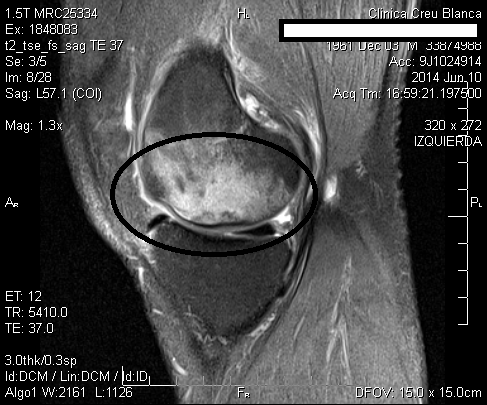

El 10/10/2014 se intervino J.C de 53 años de edad con una necrosis de condilo femoral interno. Desde hacía unos meses realizaba tratamiento de R.F., AINES y marcha con muletas para no efectuar carga de peso con la rodilla afectada. Al examen físico se observaba rodilla con derrame articular, dolorosa a la palpación (especialmente en interlínea interna femorotibial, coincidente con la necrosis), y posición viciosa en flexión. Evitaba la carga de peso por prescripción médica.

La mejoría sintomática fué casi inmediata y la evolución se hizo evidente en la RM el 4/12/2014, en menos de dos meses de realizado el tratamiento con implantes de oro. El paciente tenía unas perspectivas (según los médicos tratantes) de una baja laboral de muchos meses, con una gran incertidumbre respecto a su futuro laboral, y con un pronóstico incierto de su capacidad laboral.

A continuacion se observan las imágenes más significativas: